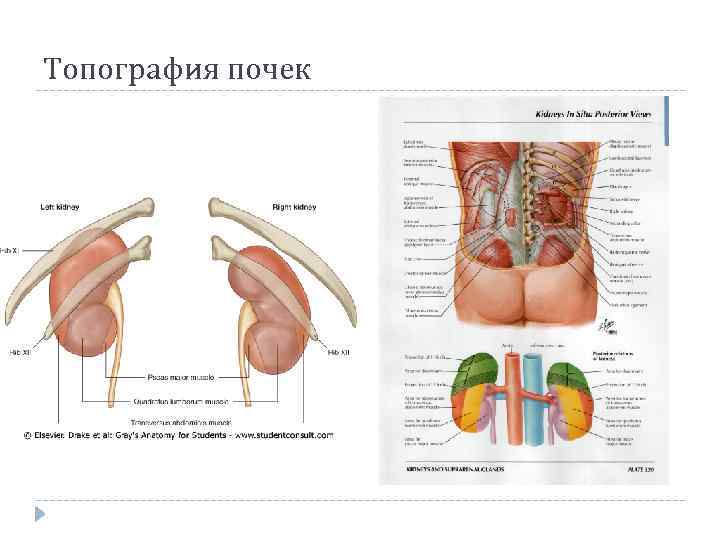

Топография почек

Топография почек